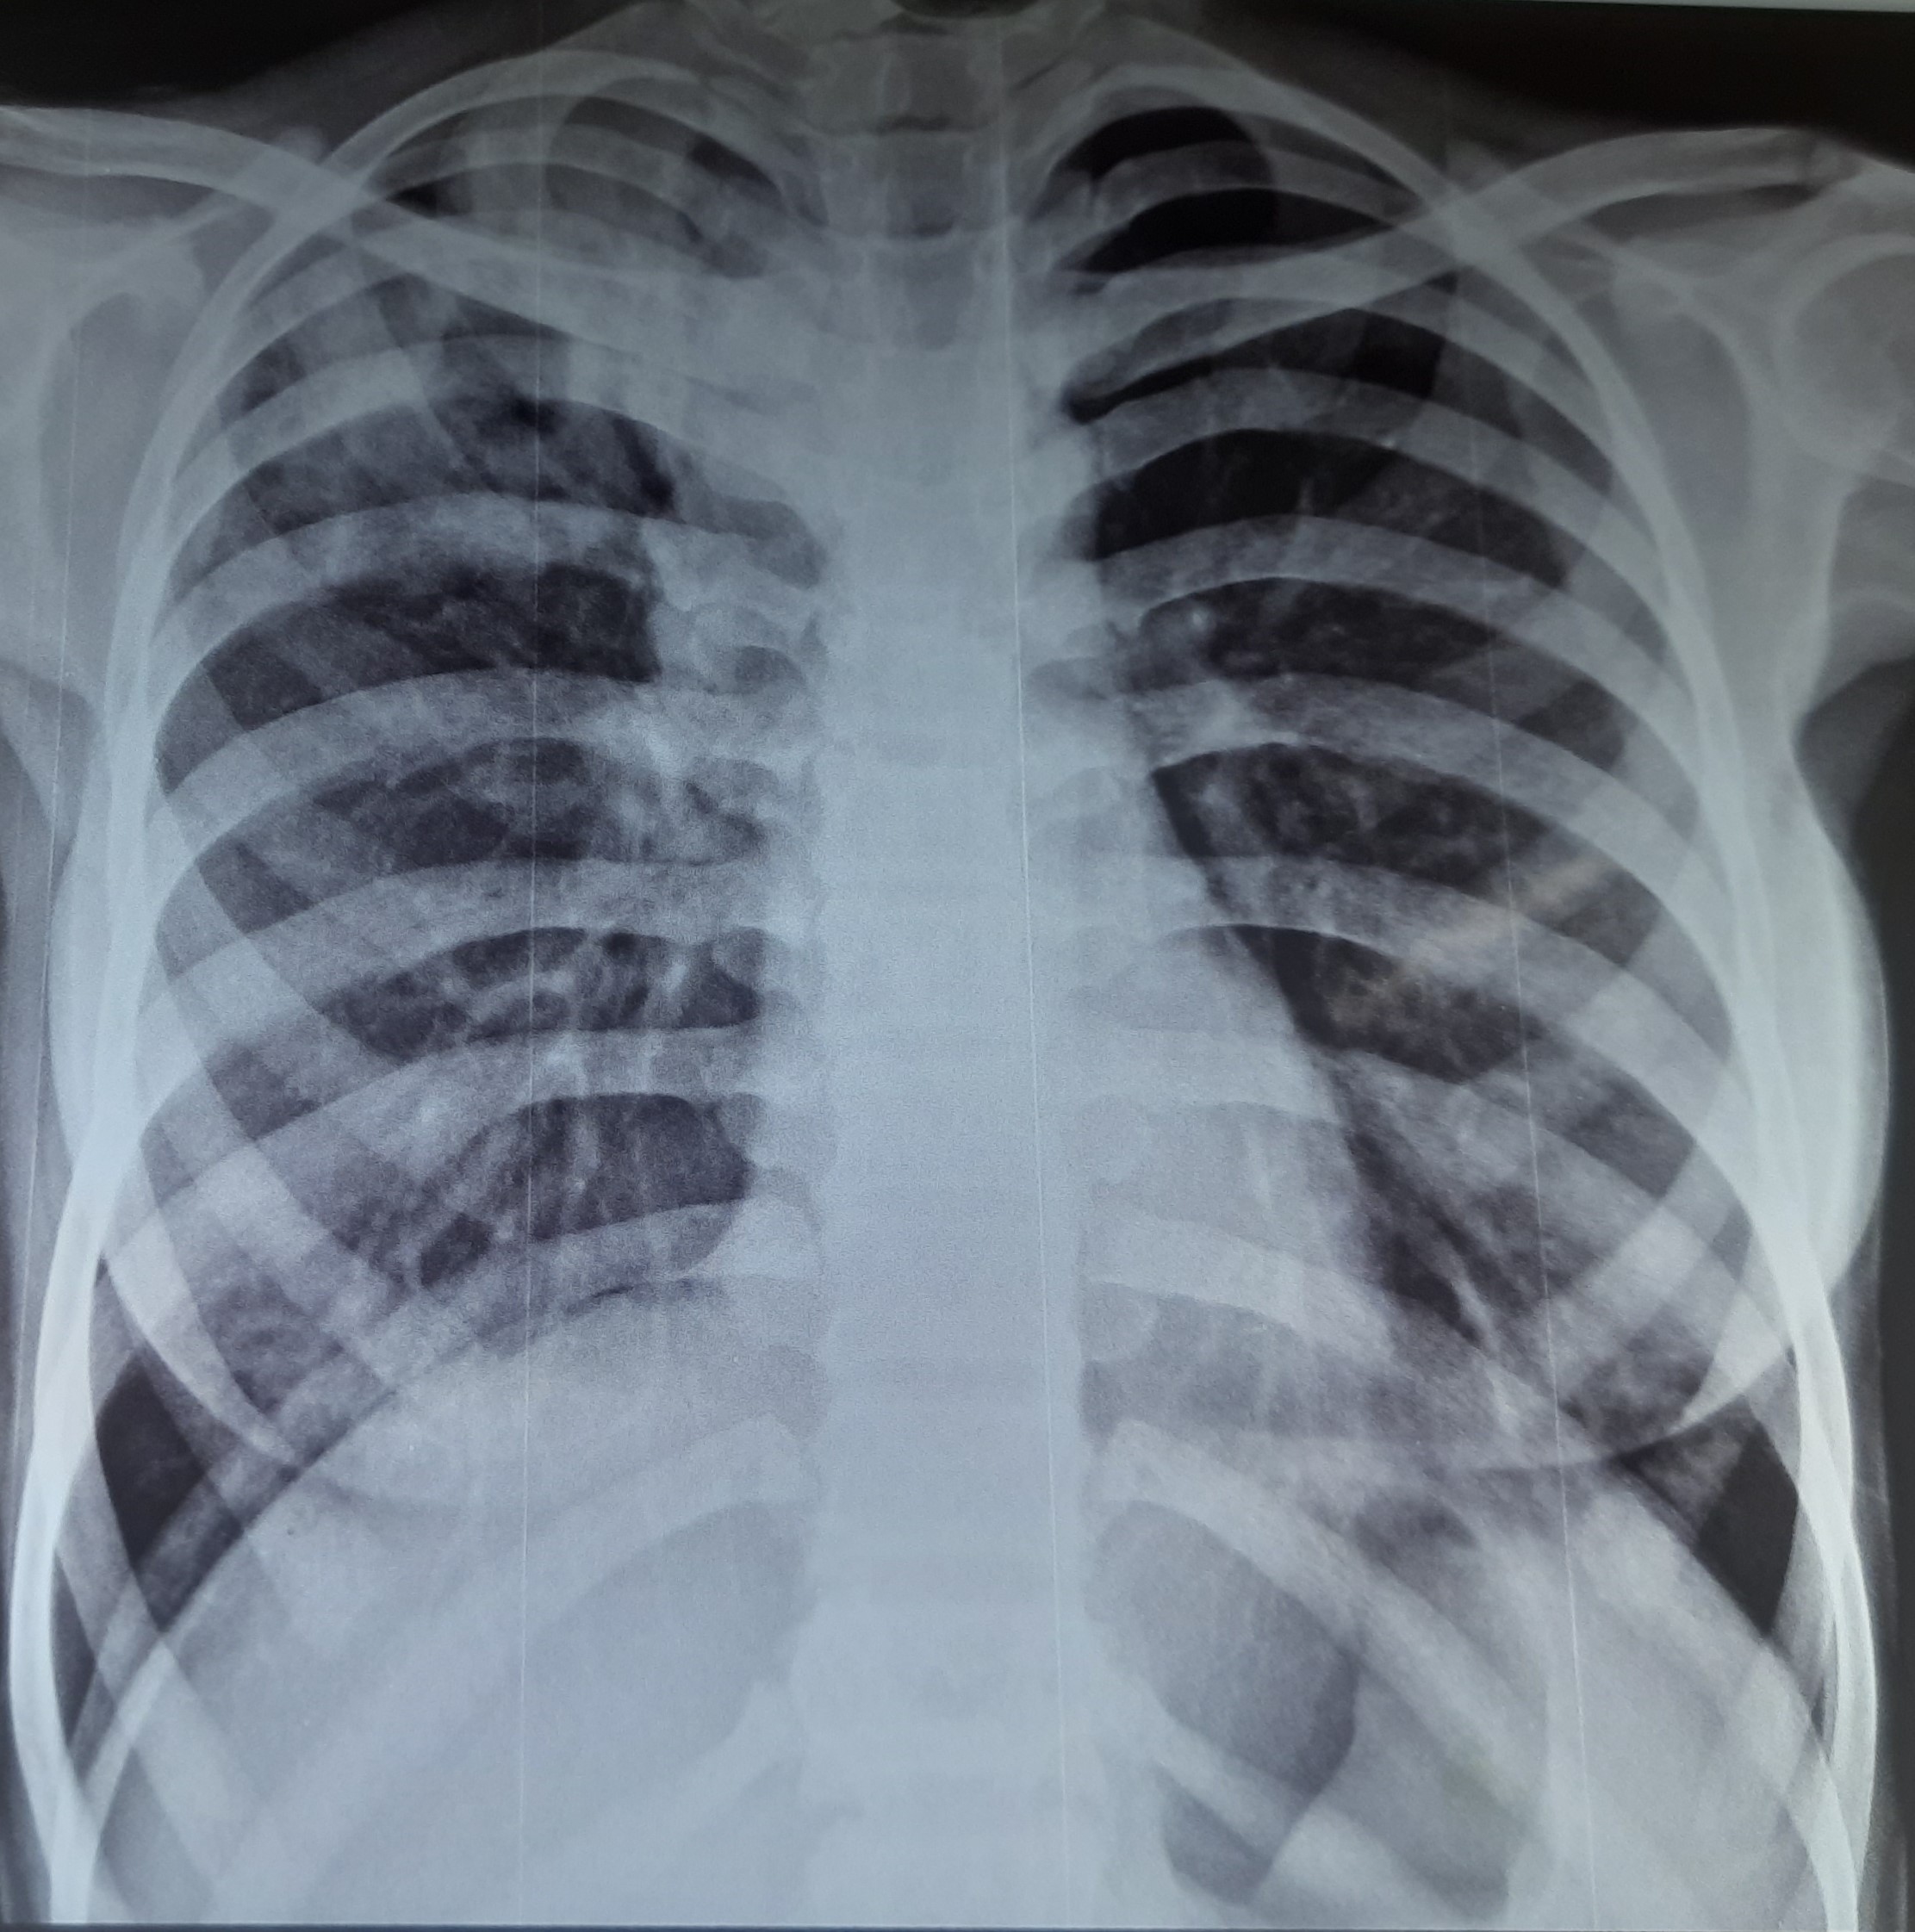

| 151 | IGGMC, Nagpur, Nagpur | P2 | 29-4321 | Chanda Bhowate | Consent taken on Paper | 42 Yrs. |

Provisional Diag : ?

Final Diag : (CxR- Right Sided Synpneumonic Effusion With Pulmonary Infiltration) |

Result awaited (Suspected TB/Non-TB) | Right CP Angle Blunting With Right Lower Zone In-Homogenous Opacity Present With Right Middle Zone/ Lower Zone Infiltration Present | Abnormality visible on x-ray |